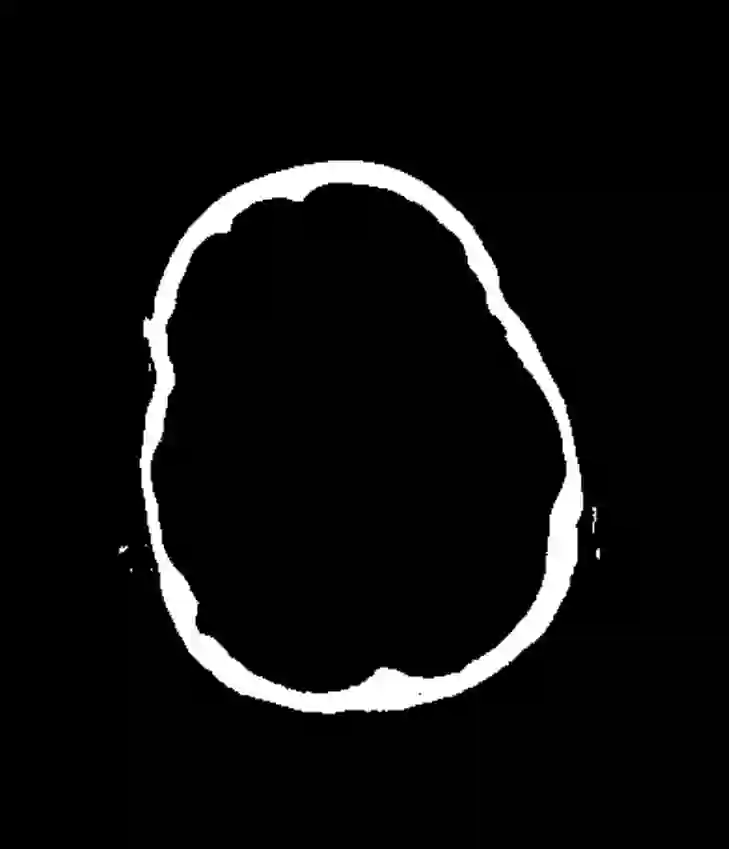

During the diagnosis of ischemic strokes, the Circle of Willis and its surrounding vessels are the arteries of interest. Their visualization in case of an acute stroke is often enabled by Computed Tomography Angiography (CTA). Still, the identification and analysis of the cerebral arteries remain time consuming in such scans due to a large number of peripheral vessels which may disturb the visual impression. In previous work we proposed VirtualDSA++, an algorithm designed to segment and label the cerebrovascular tree on CTA scans. Especially with stroke patients, labeling is a delicate procedure, as in the worst case whole hemispheres may not be present due to impeded perfusion. Hence, we extended the labeling mechanism for the cerebral arteries to identify occluded vessels. In the work at hand, we place the algorithm in a clinical context by evaluating the labeling and occlusion detection on stroke patients, where we have achieved labeling sensitivities comparable to other works between 92\,\% and 95\,\%. To the best of our knowledge, ours is the first work to address labeling and occlusion detection at once, whereby a sensitivity of 67\,\% and a specificity of 81\,\% were obtained for the latter. VirtualDSA++ also automatically segments and models the intracranial system, which we further used in a deep learning driven follow up work. We present the generic concept of iterative systematic search for pathways on all nodes of said model, which enables new interactive features. Exemplary, we derive in detail, firstly, the interactive planning of vascular interventions like the mechanical thrombectomy and secondly, the interactive suppression of vessel structures that are not of interest in diagnosing strokes (like veins). We discuss both features as well as further possibilities emerging from the proposed concept.